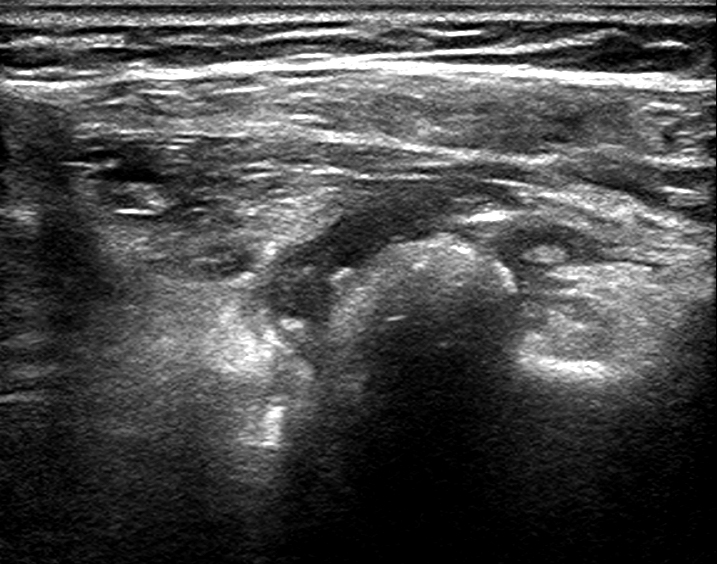

患者超声显示

抽吸物内可见白色牙膏样沉积物

10月16日我院超声科完成省内首例超声引导下钙化性肌腱炎穿刺治疗。患者系老年女性,突发左肩部疼痛不适伴上举困难2周时间,来我院就诊时左臂几乎不能外展,晚上不能睡觉,相当痛苦。经过骨科查体和超声检查后,结合病史诊断为肩胛下肌腱钙化性肌腱炎。通过我院超声介入科及骨科专家多次探讨,决定于16日下午,在超声介入室对患者行超声引导下钙化性肌腱炎穿刺治疗。治疗中在钙化结节内抽出乳白色牙膏样物体,反复冲洗,将残余物质带出,患者术后疼痛立刻缓解,上臂可以外展90°。患者对治疗效果非常满意,说回去终于可以睡个安稳觉了。据介绍,该例患者系省内首次报道的超声引导下钙化性肌腱炎穿刺治疗,为肌骨领域超声引导下治疗开创了新河。